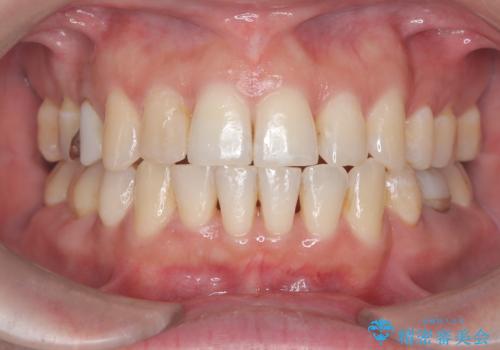

- 治療計画

- 治療計画: 重度の叢生を改善するため、上下左右の小臼歯抜歯を伴う審美ワイヤー矯正を計画しました。抜歯により得られたスペースを利用して歯を整列させ、適切な噛み合わせを目指します。途中、患者様が1年間の海外出張となったため、一時的にワイヤーを外し、保定装置で現状維持を図りました。帰国後に再度審美ワイヤー矯正を再開し、仕上げ調整を行い治療完了を目指します。

重度の叢生により、抜歯を伴う矯正が必要と判断しました。目立ちにくい透明な審美ブラケットを用いたワイヤー矯正を実施しましたが、治療途中での海外出張が決定したため、一度矯正装置を取り外し、保定装置で現状維持を行いました。帰国後に改めて装置を装着し矯正を再開。患者様のライフスタイルに柔軟に対応しながら、最終的には理想的な歯並びと美しい口元を実現しました。